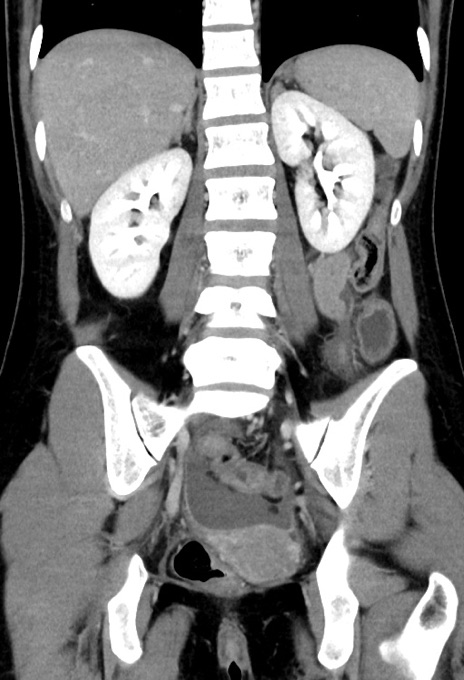

症例17(冠状断像)

【症例】20歳代女性

【主訴】嘔吐、下腹部痛

【現病歴】昨日夕食後に嘔吐し下腹部痛が出現。本日になっても嘔吐持続し改善しないため来院。

【身体所見】意識清明、BT 37.2℃、BP 108/67mmHg、腹部:平坦、やや硬、下腹部正中から右にかけて圧痛あり、反跳痛軽度あり、tapping pain(+)。

【データ】WBC 13600、CRP 14.94